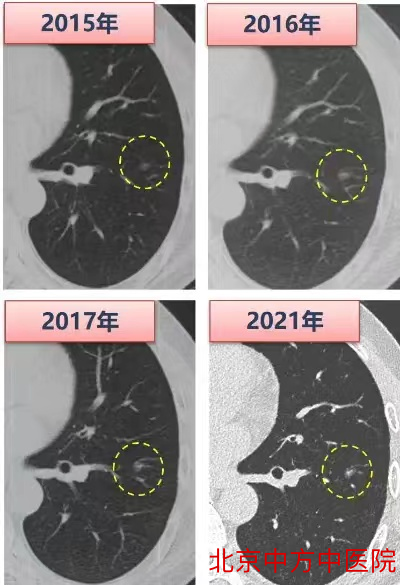

图四长期随访的磨玻璃结节实性成分增加后手术干预

我们知道,磨玻璃结节绝大部分都是惰性增殖的表现,生长非常缓慢,往往需要四五年的时间,才会发生明显变化。以一个长期随访的实际病例来说明。这个患者2015年在外院体检发现了一个小的纯GGO,此后逐年在外院随访,2017年GGO并没有明显的变化。此后患者因为工作调动,加上疫情原因耽搁了随访,再次复查时我们对比最早CT判断,结节直径虽然没有明显增长,但中心密度增高,出现了一点实性成分,进行了胸腔镜手术干预(图四)。术后病理提示是微浸润腺癌,预后很好。这个病例说明,部分小GGO在随访中可能出现进展,表现为直径增长或实性成分增加,这个过程可能很漫长,我们可以尽可能的推迟接受胸部手术的创伤,规范的随访观察是很安全的。